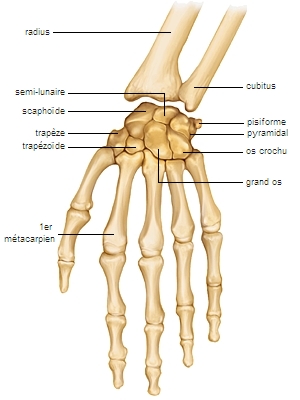

carpe LAROUSSE